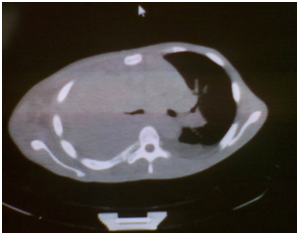

Simple CT scan of skull, thorax and abdomen

Skull: Not encephalic alterations for this study

Lung asymmetry for hipodensity area of lung with tumoral aspect in half or inferior third of the right lung that impresses to obliterate for infiltration the bronchus of the right inferior lobe. This lung mass of lobulated contours and in some espiculated areas, in their inferior end it melts with the mediastinum. They also exist other lung nodules of sub-pleural localization that go from 7 to 15mm, also at pleural level exists thickness of the same one, of nodular aspect, where acquires its biggest thickness right anterobasal ending up measuring 52mm. Slight right pleural effusion, multiple adenophaties in conglomerate in the whole mediastinum from the region infraclavicular. Non alterations in the left lung. Elevation of the right hemidiafragm, not suprarenal lesion, not lesion ocupative of the hepatic space, don't injure of lumbar bone.

This type of malignant tumor is more frequent at level of the parietal pleura, toward inferior portions with a pattern of diffuse growth, it encapsulates the whole lung and it invades thoracic structures; clinically it is presented with pleural effusion recidivist and thoracic pain.11 In our patient the thoracic pain was the initial element that due to the character and the irradiation was interpreted as a somatic etiology. Clinical element that suggest a tumoral diagnosis were the duration and worsened of pain on the time. On physical examination the thoracic expansibility diminished in all right hemithorax and the presence of adenophaties with tumoral consistence in the same side to lend support this etiology (Table 3). In the other hands elements that questioned the diagnosis firstly were the mediastinal participation and the presence of bronchial infiltration (Figure 1) that is usually more frequent in the lymphoma and in the bronchogenic tumor respectively. Besides the patient's age. The quantity of the pleural effusion was always scarce. Imagenological elements to favour was the marked pleural thickness, the nodular pattern of the same one and the left displacement of the mediastinum (Figure 2). Humoral element that support the diagnosis were the anemia, thrombocytosis and decreased iron level (Table 4) characteristic of this type of process. Although a marker unique immunohistochemistry doesn't exist with the enough specificity to carry out the diagnosis of malignant mesothelioma, the common thing is to use a panel of markers. It should be considered that the pancitoqueratinas tints to most of the mesothelioma. For mesothelioma epithelioid the positive markers include the calretinina, Citoqueratinas (CK) 5/6, the nuclear Wilms tumor Antigen type 1 (WT-1) and the podoplanina (D2-40). For the adenocarcinoma are used the carcinoembrionary antigen, Ber-EP4, TTF-1 and napsina A,12 which confirmed the definitively diagnosis in this patient. In relation to the treatment, the radiotherapy and the chemotherapy have shown little influence on the survival are high the mortality and the surgical morbidity (near at the five and 50%, respectively). The main objective of this it consists on palliating the main symptoms, the dysnea and the thoracic pain, it can include chemotherapy, radiotherapy and the surgical intervention (or both).13 In this case we decided to begin treatment with Carboplatino 350 mg/m2/day, Paclitaxel 175 mg/m2/day and Vinblastina 6 mg/m2/day all regimens each 21 days. Because the combination of several chemotherapy including a Platino compound may result more effective than the monotherapy,14, 15 being able to improve partially the symptomatology.

Figure 1 Simple CT Scan that show lung asymmetry for hipodensity area of lung with tumoral aspect that impresses to obliterate for infiltration the bronchus of the right inferior lobe.